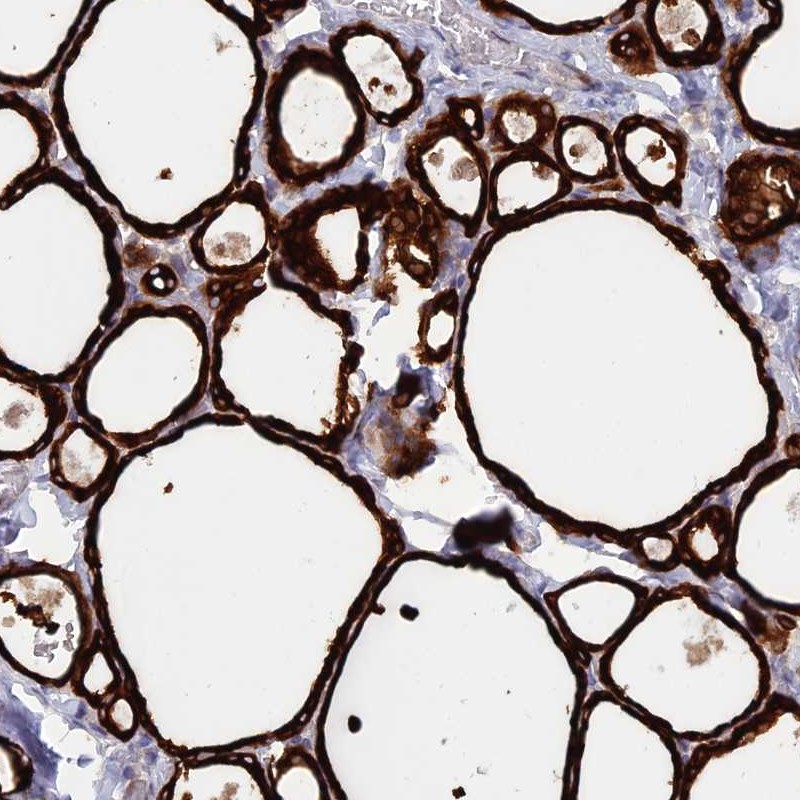

Immunohistochemical staining of human thyroid gland shows strong cytoplasmic positivity in glandular cells.